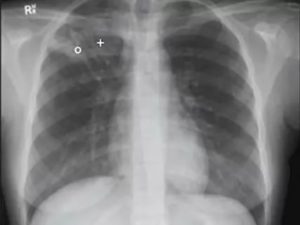

Кальцифицированные лимфоузлы на рентгене

Гистология биоптата покажет наличие или отсутствие эпителиоидных гранулём. При туберкулёзе лёгких с воспалением лимфатических сосудов в органах дыхания может находиться кальцинированный шлак.

Его выявляют специальной диагностикой.

Для диагностики заболевания используют лабораторные анализы, бронхоскопию и рентгеноскопию, рентгенографию. Но видны ли лимфоузлы на рентгене? В нормальном состоянии нет, то стоит им увеличиться в размерах и рентгенолог без труда рассмотрит их на снимке.

Увеличение лимфоузлов средостения на рентгенограмме выглядит как «патологическая тень», с помощью обследования доктор может сделать заключение о размещении очага воспаления или новообразования, его форме, подвижности. Также рентген помогает определить, оказывает ли заболевание негативное воздействие на внутренние органы, расположенные рядом.

Увеличенные лимфоузлы на рентгене часто изображены в форме уплотнений, часто патология сопровождается увеличением корней легких.